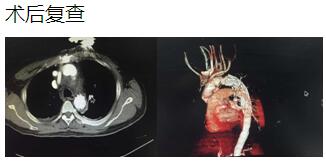

通訊員 李小升 報(bào)道:近日,衡陽市中心醫(yī)院心胸外科成功完成一例淺低溫停循環(huán)下“孫氏手術(shù)”(升主動(dòng)脈置換、主動(dòng)脈弓置換、降主動(dòng)脈術(shù)中支架置入)。

患者是一位48歲中年男性,因胸痛1小時(shí)入院,我院CT提示主動(dòng)脈夾層累及胸、腹主動(dòng)脈全層,診斷為主動(dòng)脈夾層(D ebaKey I型)?;颊卟∏槲V兀中g(shù)治療是挽救其生命的唯一希望。為了挽救病人生命,經(jīng)過麻醉科、手術(shù)室、體外循環(huán)組的術(shù)前充分討論,心胸外科廖金文主任、廖承輝副主任帶領(lǐng)團(tuán)隊(duì)決定為其施行復(fù)雜而高難度的淺低溫停循環(huán)下“孫氏手術(shù)”。術(shù)中見主動(dòng)脈全程及三分支受累,右冠受累,冠脈開口受壓狹窄,予以行“升主動(dòng)脈 主動(dòng)脈弓置換 降主動(dòng)脈術(shù)中支架置入術(shù)”,團(tuán)隊(duì)成員歷經(jīng)約10個(gè)小時(shí)的奮戰(zhàn),手術(shù)順利完成。術(shù)后六小時(shí)患者意識(shí)完全清醒,現(xiàn)在已完全康復(fù)。